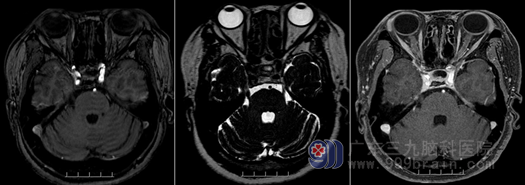

欧阳主任对刘姨说:三叉神经痛号称“天下第一痛”,其发病原因比较复杂,常见的原因有:血管压迫、病毒性疱疹、肿瘤侵犯等。从刘姨的检查,特别是磁共振结果来看,可排除肿瘤等继发性因素引起,MR可见右侧三叉神经颅内段根部外侧有一小血管水平伴随走行,考虑血管压迫神经,这种原发性三叉神经痛正是刘姨出现剧烈面痛的原因。